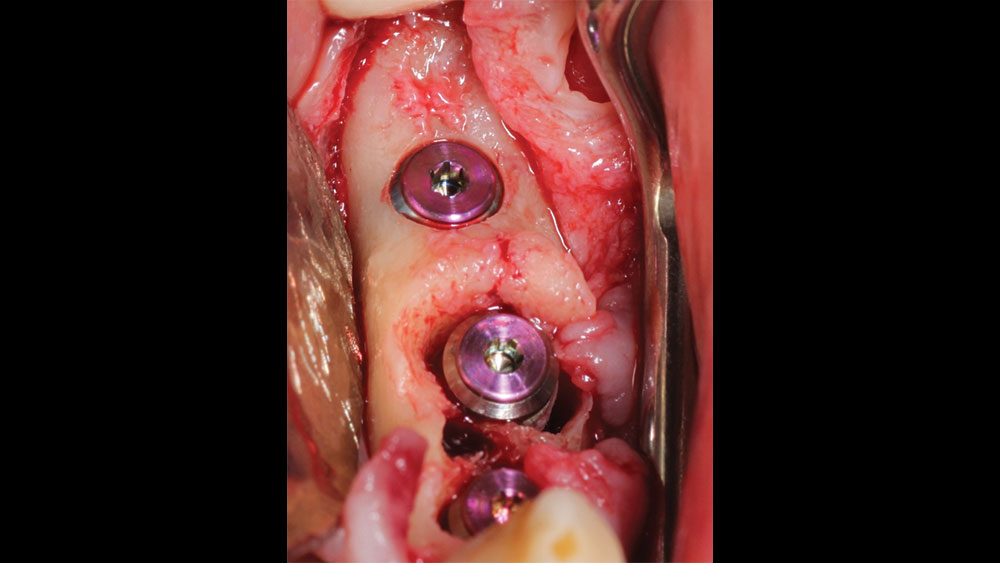

In this case, the patient presented with pain in the lower left posterior quadrant of her mouth. Upon examination, it was discovered that she had two failing premolars side by side, both of which had received cast restorations several years in the past. Failure was due to recurrent decay beneath those restorations. Her molar #19 had also been removed several years ago, resulting in a span where three adjacent teeth required replacement.

The patient selected implant treatment to replace her teeth. Screw-retained crowns were chosen instead of a cementable restoration, primarily due to the ease of retrievability afforded by screw retention. Because the posterior location of the restorations required resistance to occlusal forces as well as acceptable esthetics, I selected BruxZir® zirconia as the material; its high flexural strength and natural translucency fulfilled both requirements.